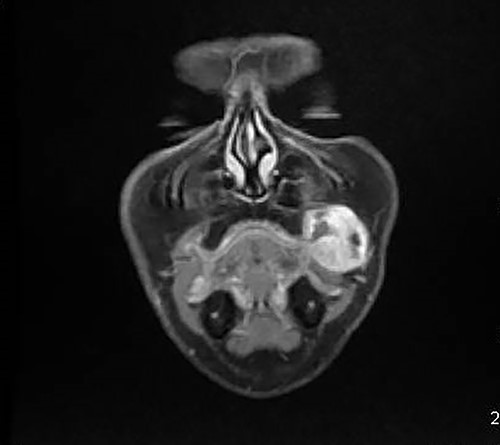

A 46-year-old woman, without clinical antecedent, presented with a tumor in the inner side of the left cheek which had rapidly grown for 3 weeks. Physical examination revealed an ulcerating mass measuring 4 × 3.5 cm, well-circumscribed, fleshly, with a white surface. There was submandibular lymphadenopathy, ranging in dimension from 1 to 1.5 cm in diameter. Magnetic resonance imaging (MRI) scan revealed the tumor of the cheek without mandibular bone infiltration or sinonasal involvement (Fig. 1). Chest computed tomography and abdominal ultrasound scan were unremarkable. An excisional biopsy was performed. Pathological examination showed a neoplastic proliferation composed of mixture of mature benign epithelial components, such as intestinal type, respiratory and squamous epithelia, and mature mesenchymal components, such as muscular tissue and cartilage (Fig. 2) and neuroglial tissue. In addition, immature and malignant tumor components were found such as small blue tumor cells resembling primitive neuroectodermal tumor (Fig. 3), adenocarcinoma and sarcoma with muscular and cartilaginous differentiation (Fig. 4). This tumor infiltrates the skeletal muscle with free margins. Immunohistochemically, epithelial components were positive for pankeratin; mesenchymal components showed desmin, myogenin and S-100 positivity and the primitive neuroectodermal tumor component was positive for NSE, CD99, GFAP, synaptophysin and focally for chromogranin. SALL4 was negative. The resected submandibular lymph nodes were devoid of malignant infiltrate. The diagnosis of TCS was established and the patient was treated by combined chemotherapy (cisplatine +5 fluorouracil) and radiation therapy. No recurrence was noted 6 months after treatment.

Mature glandular components with cartilage (magnification at ×40).